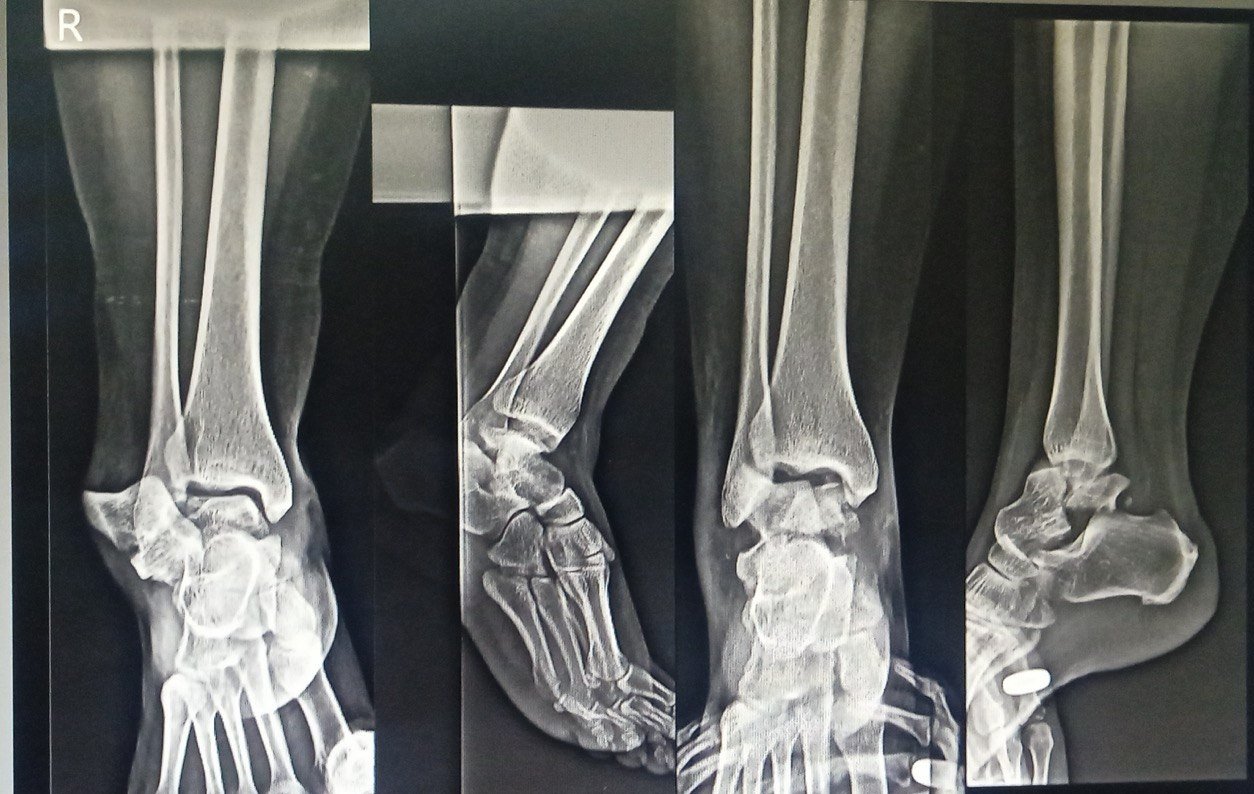

Expert care for all your foot and ankle problems. From injuries to long-term pain, Dr. Vishal Yadav provides personalized treatment to help you walk pain-free and live better.

Minimally Invasive Surgery (MIS) :

- Ankle Arthroscopy

- Endoscopic Calcaneoplasty

- Posterior Arthroscopy